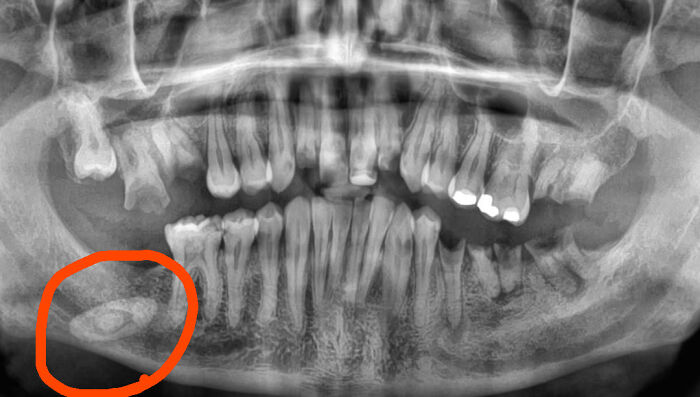

#45 My X-Ray Before I Got My Teeth Fixed Revealed A Extremely Large Saliva Gland Stone

Image source: Chosensoul444